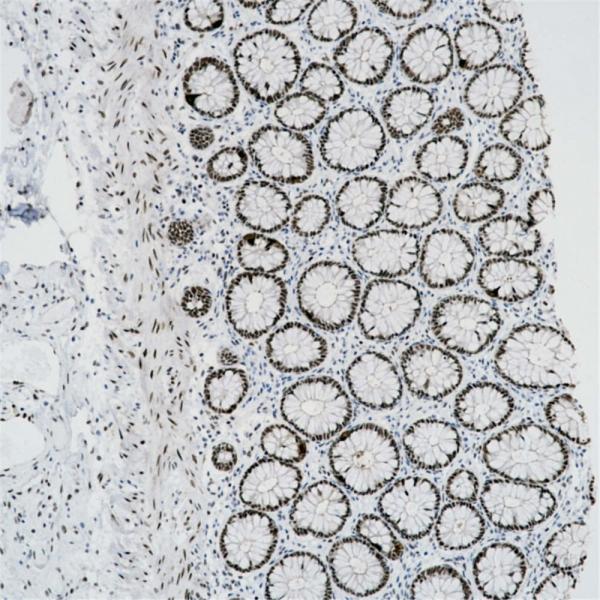

FABP3

BP6313

FOXL2

BP6235

FOXP1

BP6112

FOXP3

BP6166

FRα

BP6286